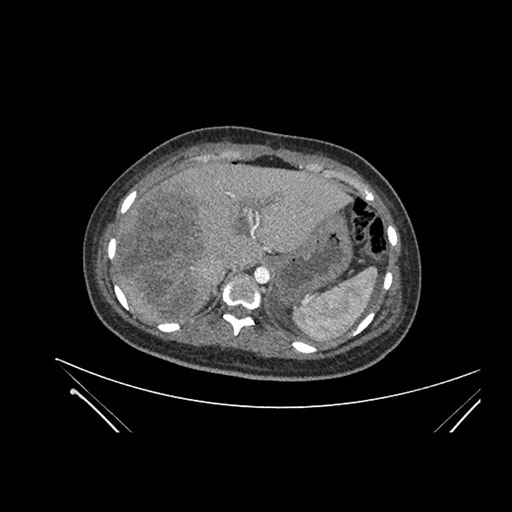

Imaging Analysis

Look through the patient's CT scan to identify any areas of concern for the necessary procedure.

Coronal Venous